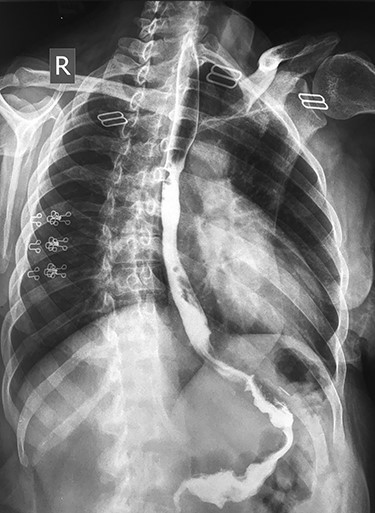

Endoscopic esophageal stent placed for 2 months, with improvement of the clinical condition; after stent removal, she presented with dysphagia, barium study showed esophageal stricture at the middle third of the esophagus at the site of the upper margin of the stent (Fig. 1).

Barium study showing stricture at the middle third of the esophagus with proximal dilatation.